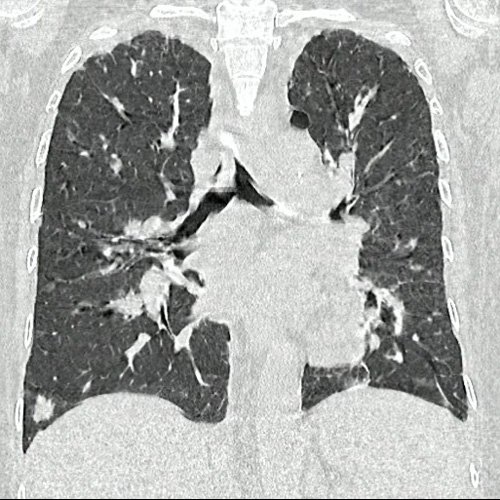

• TAC de tórax sin contraste - informe preeliminar (Dia 31):  Estudio artefactado por movimientos respiratorios de la paciente. Se observan múltiples lesiones nodulares sólidas, irregulares, heterogéneas, que se extienden por ambos campos pulmonares a predominio derecho, de manera periférica y subpleurales, asociadas a vidrio esmerilado, destacándose la de mayor tamaño en segmento lingular inferior que mide 12 mm x 16mm. Hallazgos que podrían corresponder en primera instancia a proceso inflamatorio infeccioso sin poder descartar secundarismo. Se sugiere control evolutivo.  Hallazgos no visualizados en Tc del día 05-08-2025, si se observan en TC del día 24-09-2025. Bulla subpleural paramediastinal, de 14mm, en segmento posterior del LSI. Leve derrame pleural, en esta ocasión, bilateral, de mayor jerarquía a derecha. Múltiples estructuras ganglionares pre y lateroaórticas, axilares bilaterales aumentada en número y de tamaño, de rango no megálico. Laminar derrame pericárdico.

Por presentar persistencia de dolor abdominal inespecífico, se solicita tomografía con contraste la cual informa hepatomegalia concordante con palpación abdominal (5 traveses de dedo por debajo del reborde costal), aumento de tamaño de lesión hepática previa y nuevas lesiones asociadas. En la tomografía de tórax se visualiza la presencia de nuevas imágenes nodulares sólidas, irregulares y heterogéneas distribuidas en ambos campos pulmonares.

TAC de tórax (Dia 31)